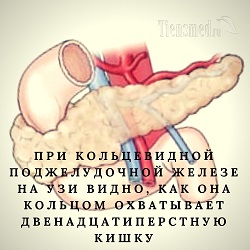

УЗИ диагностика кольцевидной поджелудочной железы: что важно знать